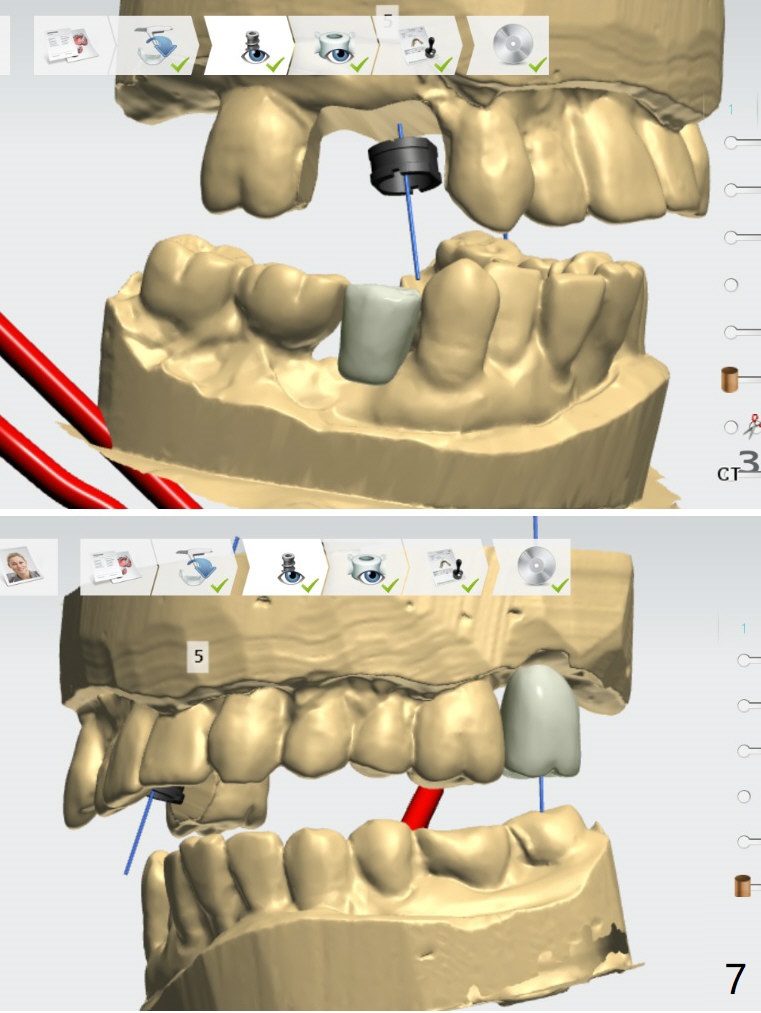

Because of the narrow space at #4 and 5, an implant will be placed slightly distal of #5 site and a cantilever FPD will be made at #4 and 5.